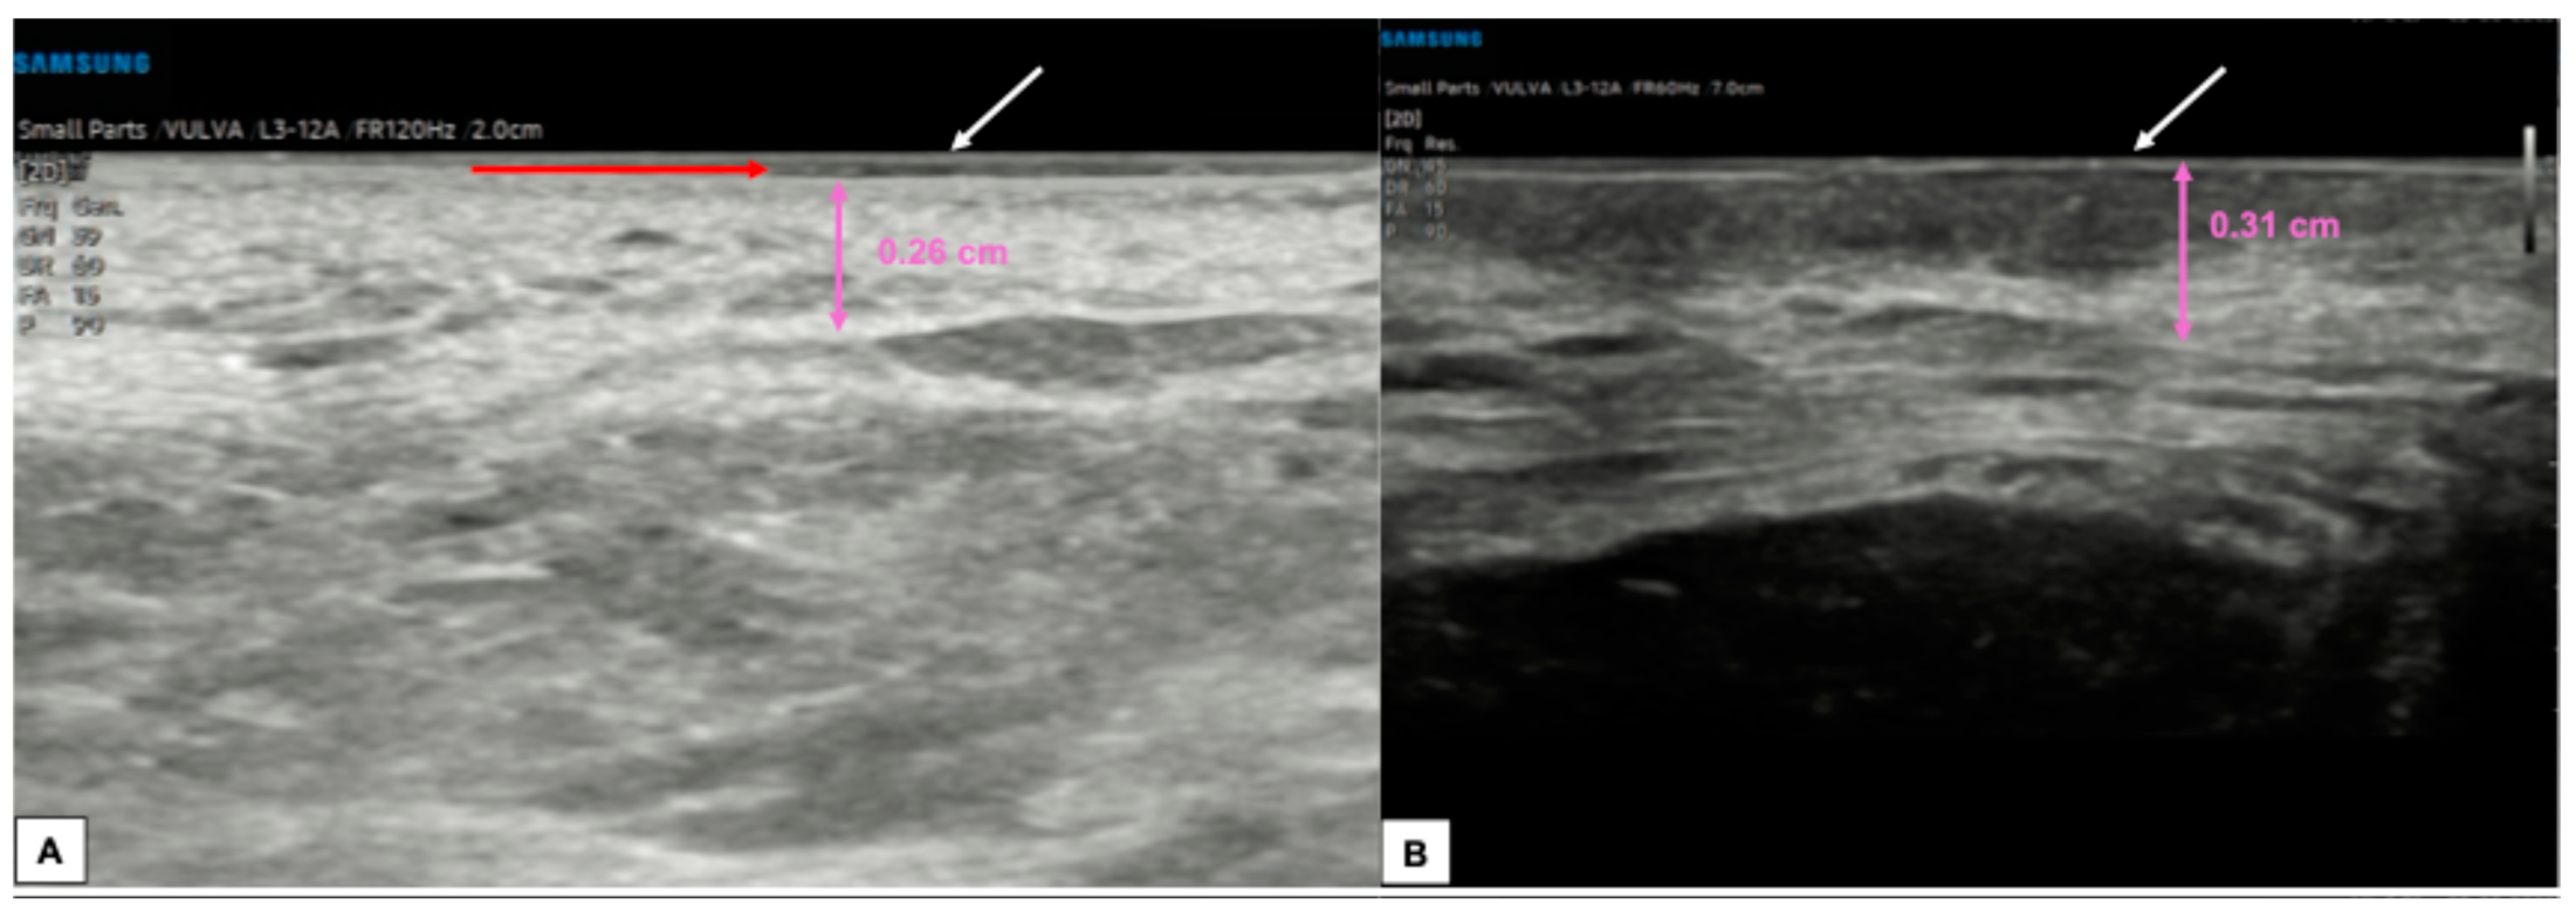

6.1. Epidermis

6.2. Dermis

6.3. Hypodermis